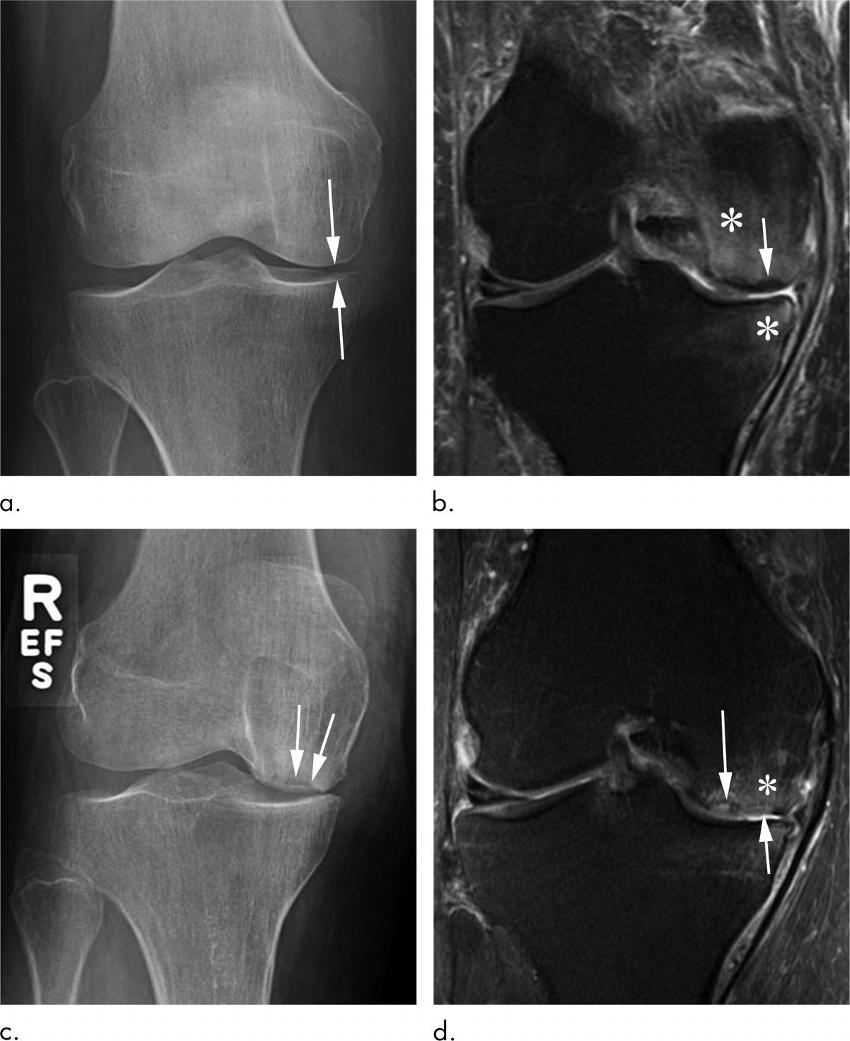

Figure 3. Subchondral insufficiency fracture in a 69-year-old woman who presented with acutely worsening knee pain without known trauma. (a) Anteroposterior radiograph of the right knee shows possible medial compartment joint space narrowing (arrows) without osteophytes. There are no signs of osteonecrosis or subchondral insufficiency fracture. (b) Coronal intermediate-weighted fat-suppressed MRI obtained at the same time as a shows a subchondral insufficiency fracture of the medial femoral condyle, without collapse of the articular surface (arrow). In addition, there is marked femoral and tibial bone marrow edema (*). This patient was not treated with conservative measures (ie, switch to non–weight-bearing activity) and received an intra-articular corticosteroid injection. (c) Eleven months later, she returned with continued right knee pain. Repeat anteroposterior radiograph of the right knee shows collapse of the medial femoral condyle articular surface (arrows). (d) Coronal intermediate-weighted MRI acquired at the same time as c demonstrates deformity of the articular surface (short arrow) of the medial femoral condyle in the area of a previously noted subchondral insufficiency fracture (long arrow). In addition, there is marked bone marrow edema (*).